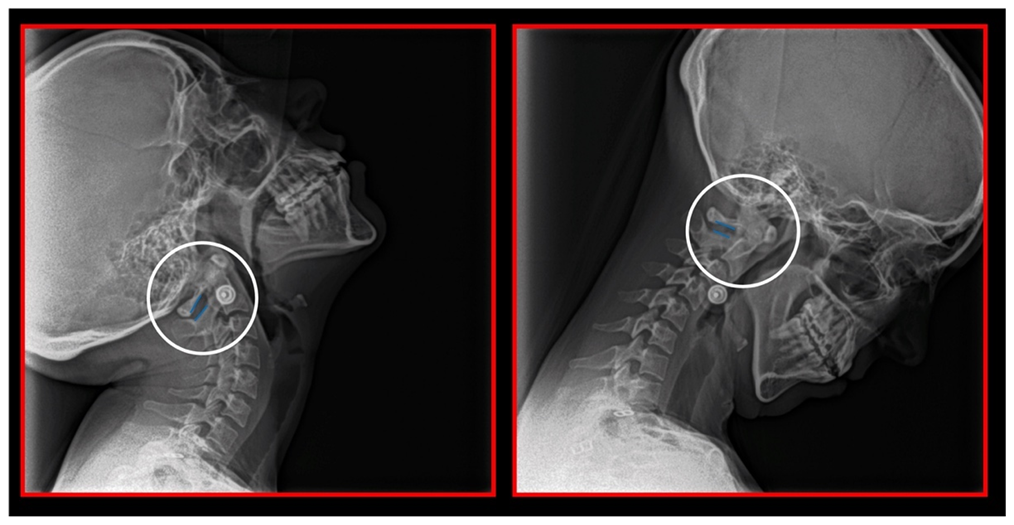

11.5. Axis and Atlas Derotation